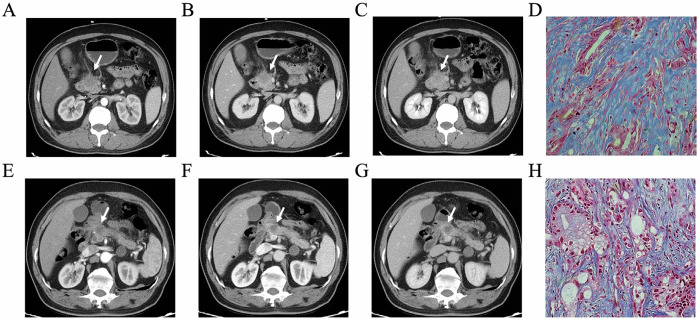

Methods: Patients with resected PDAC were retrospectively included from three institutions. Evaluating tumor fibrosis content using fibrotic pixels proportion through Masson staining of postoperative pathological sections. Radiomics features from preoperative contrast-enhanced CT (CECT) were extracted and used to develop models in the training cohort. The diagnosis performance was further validated in the two test cohorts. The outcome cohort, including patients with advanced PDAC undergoing neoadjuvant chemotherapy, was used to evaluate the predictive value of the model for overall survival (OS) and disease-free survival (DFS), which were investigated using the Kaplan-Meier method and log-rank test. RNA sequencing data from a prospective biological basis cohort were conducted to explore the biological processes underlying the radiomics model.

Results: Among 215 patients (median age 60.89 years, 142 men) used for radiomics modeling, 132 (61.40%) were confirmed as high fibrosis content. The combined phase (CP) radiomics model, which included all CECT radiomics features, showed the best performance for predicting fibrosis grade, with AUCs of 0.831, 0.785, and 0.746 in training, internal test, and external test cohorts. OS (p = 0.011) and DFS (p = 0.022) can be categorized using the CP radiomics model in the outcome cohort. RNA-seq indicated that different CP models were associated with fibrotic production and remodeling processes.